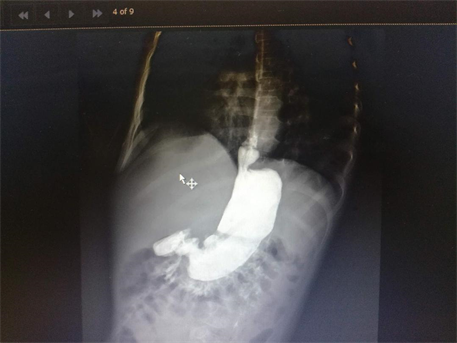

Medical records of 11 patients who underwent total esophagogastric separation (TEGS) with Roux en Y anastomosis for recurrent GERD in our institute in pediatric surgery unit, Medina children hospital, KSA during the period between Feb. 2011 to March 2018 were reviewed retrospectively. Selective criteria included all cases of recurrent GERD in NIC after fundoplications. TEGS was not performed in any case as a primary procedure. Their ages range between 6 - 14 years. Seven cases did TEGS for recurrent GERD symptoms after three fundoplications in three cases and two fundoplications in four cases. The recurrence of GERD was assessed clinically and radiologically. Clinical assessment was done by following cases of previous fundoplications as regarding improvement of body weight, signs of malnutrition, feeding tube problems, in addition to recurrent attacks of respiratory tract infections. Upper gastro-intestinal contrast studies were carried out to diagnose cases of recurrent reflux and give an idea about wrap strength (Figure 1 and Figure 2). Milk scan was needed for confirmation of GERD induced respiratory problems.

Figure 2. Wrap disruption in failed Nissen fundoplication.